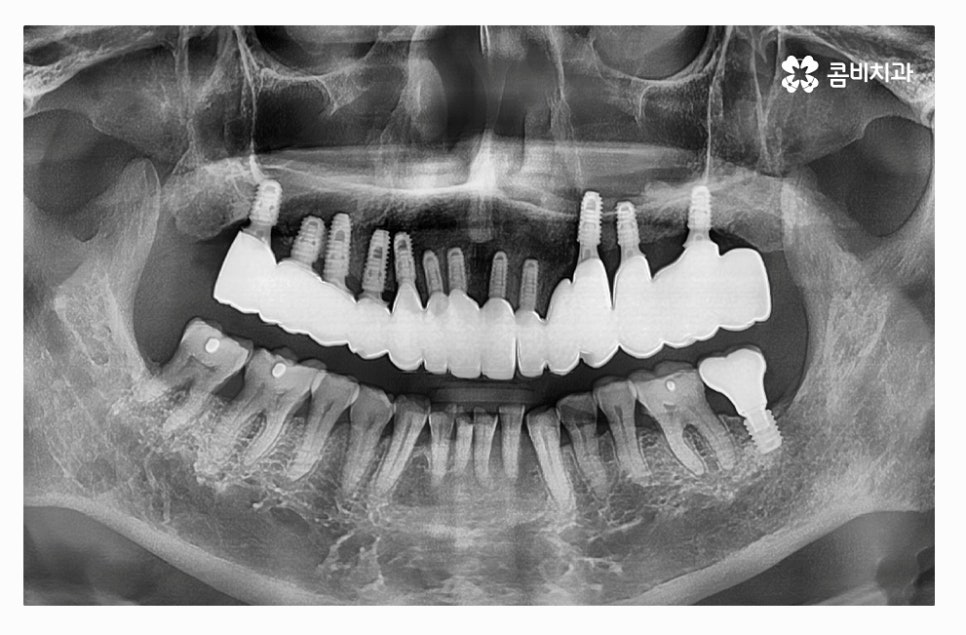

오늘 보여드릴 사례의 경우 치주질환과 염증으로 인해서 윗니를

모두 잃게 되어 전체임플란트 시술을 하게 된 사례라고 할 수 있는데요.

과거에는 치아를 한꺼번에 상실한 경우 틀니를 하는 경우도

많았지만 요즘은 대부분 전체임플란트 시술을 통해서

심미성과 함께 저작력을 회복시키고 있는데요.

만성치주염 환자분들의 경우 치아를 한꺼번에 발치한 후에

전체임플란트 치료 과정을 거치는 것 자체가

고난도의 시술이며 비용도 만만치 않지만

치료를 안전하게 마무리하고 수명을 오랫동안

건강하게 유지하는 것이 무엇보다 중요하다고 할 수 있는데요